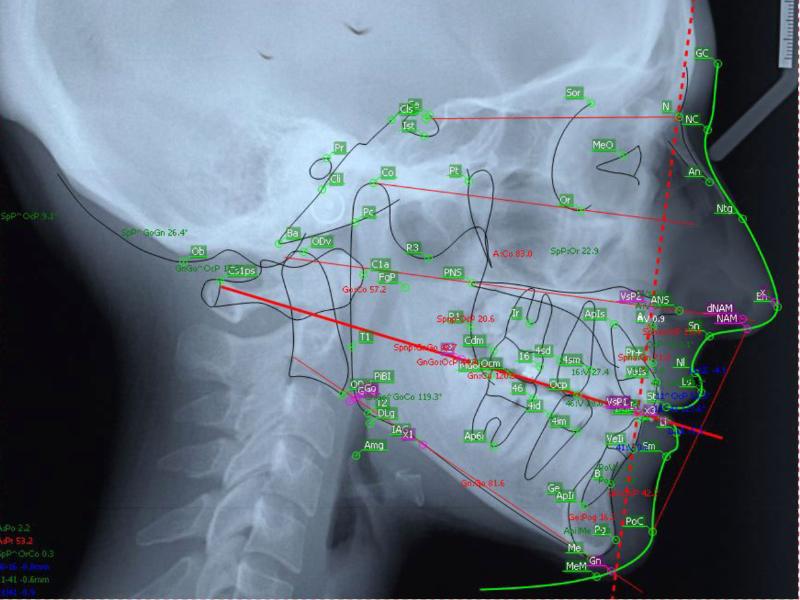

A cirurgia ortognática é um procedimento orto-cirúrgico com o intuito de restabelecer um padrão dentário e facial harmônicos, em pacientes que apresentam alterações no desenvolvimento dessa região. Destacamos uma significativa melhora nos seguintes casos: oclusão (mordida), respiração, DTM´s (disfunções temporomandibulares), harmonia da face. Cirurgia ortognática é um tratamento realizado por meio da combinação de movimentos dentários (ortodontia) e reposicionamento das estruturas dos maxilares (cirurgia). Aproximadamente 20% da população e apresentam vários graus de comprometimento estético e funcional.